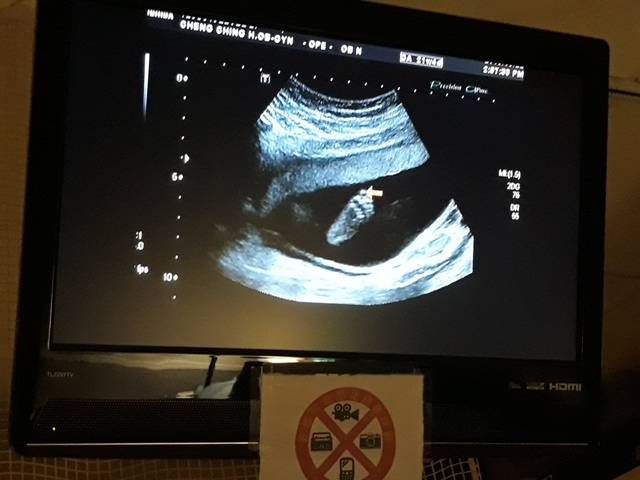

妊娠糖尿病數值為124,超過140就是超標,小純的妊娠糖尿病檢驗結果為正常的數值。接著,去照超音波,自從05月22日和06月03日的產檢,發現小飛的FL(腿長)比實際天數少一個星期後,讓小純感到很鬱悶,他最近很努力的吃鈣片,希望能讓小飛的腿長趕上進 度,今天一量,27週又0天,雖然還是落後實際的天數(27週又3天),但已漸漸趕上了。

在照超音波時,關醫師說小飛用手把臉給遮住了,所以看的不是很清楚。之前小飛所測的心跳都是150起跳,今天所測的心跳數為141(備註:在網路上查到說,胎兒隨週數不同而每分鐘的心跳數不同;正常而言,前三個月每分鐘為160~180次,中期三個月為每分鐘140~160次,最後三個月由於胎兒的神經系統逐漸發育成熟,每分鐘的心跳降為120~160次,直到出生為止。)。

27週又3天↓